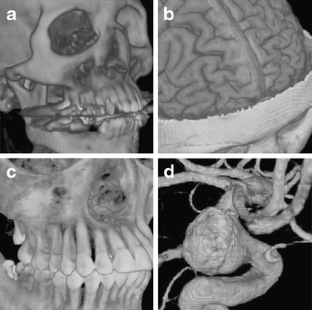

Fig 2.